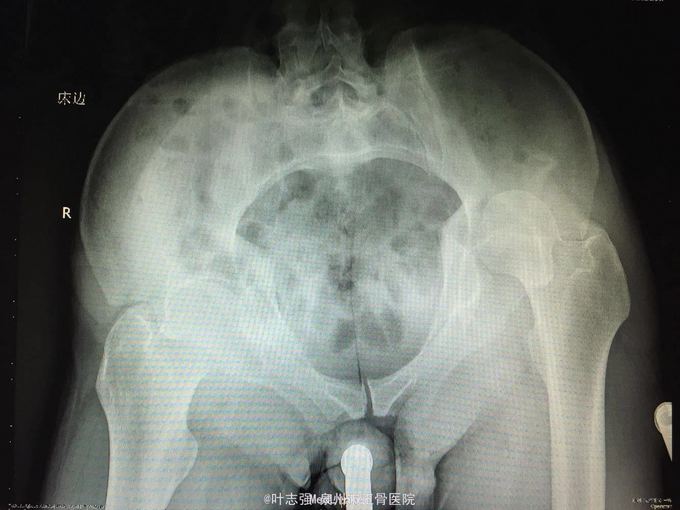

髋臼骨折伴髋关节后脱位ORIF

车祸致左髋部疼痛、活动受限1天。 53岁男性

左髋臼骨折伴髋关节后脱位 行生命支持,股骨髁上骨牵引,

股骨头坏死概率?